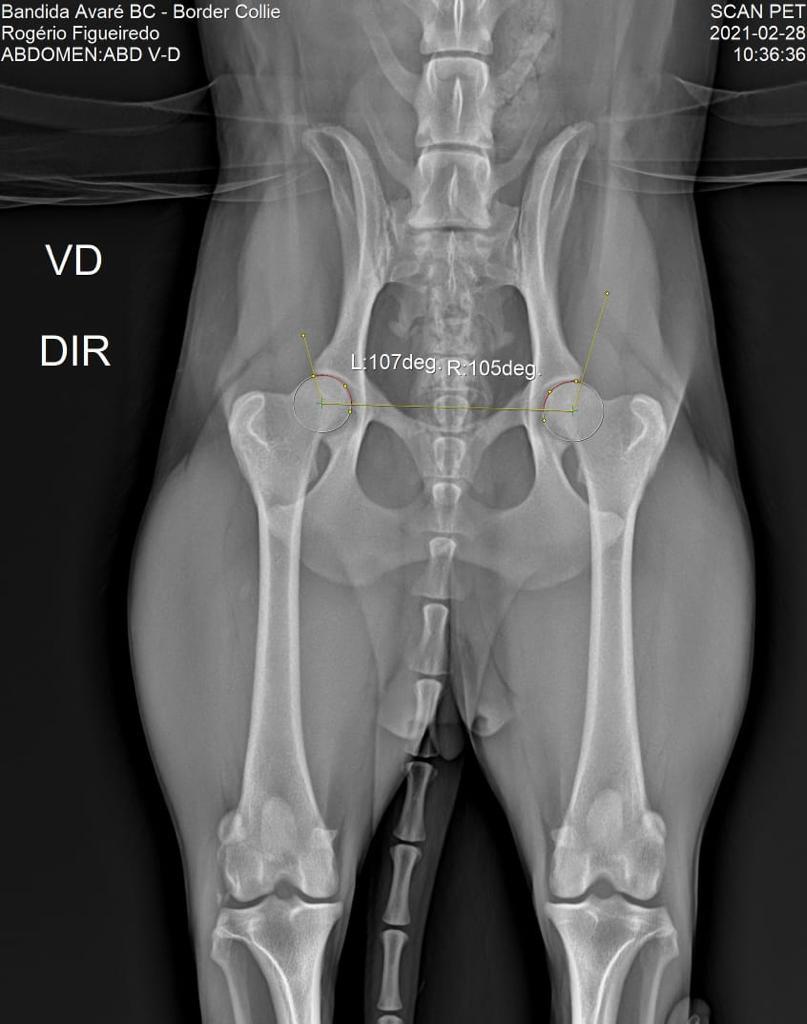

DISPLASIA

28/02/2021

ADEQUADO GRAU A

SCANPET

LAUDO

CHAPA